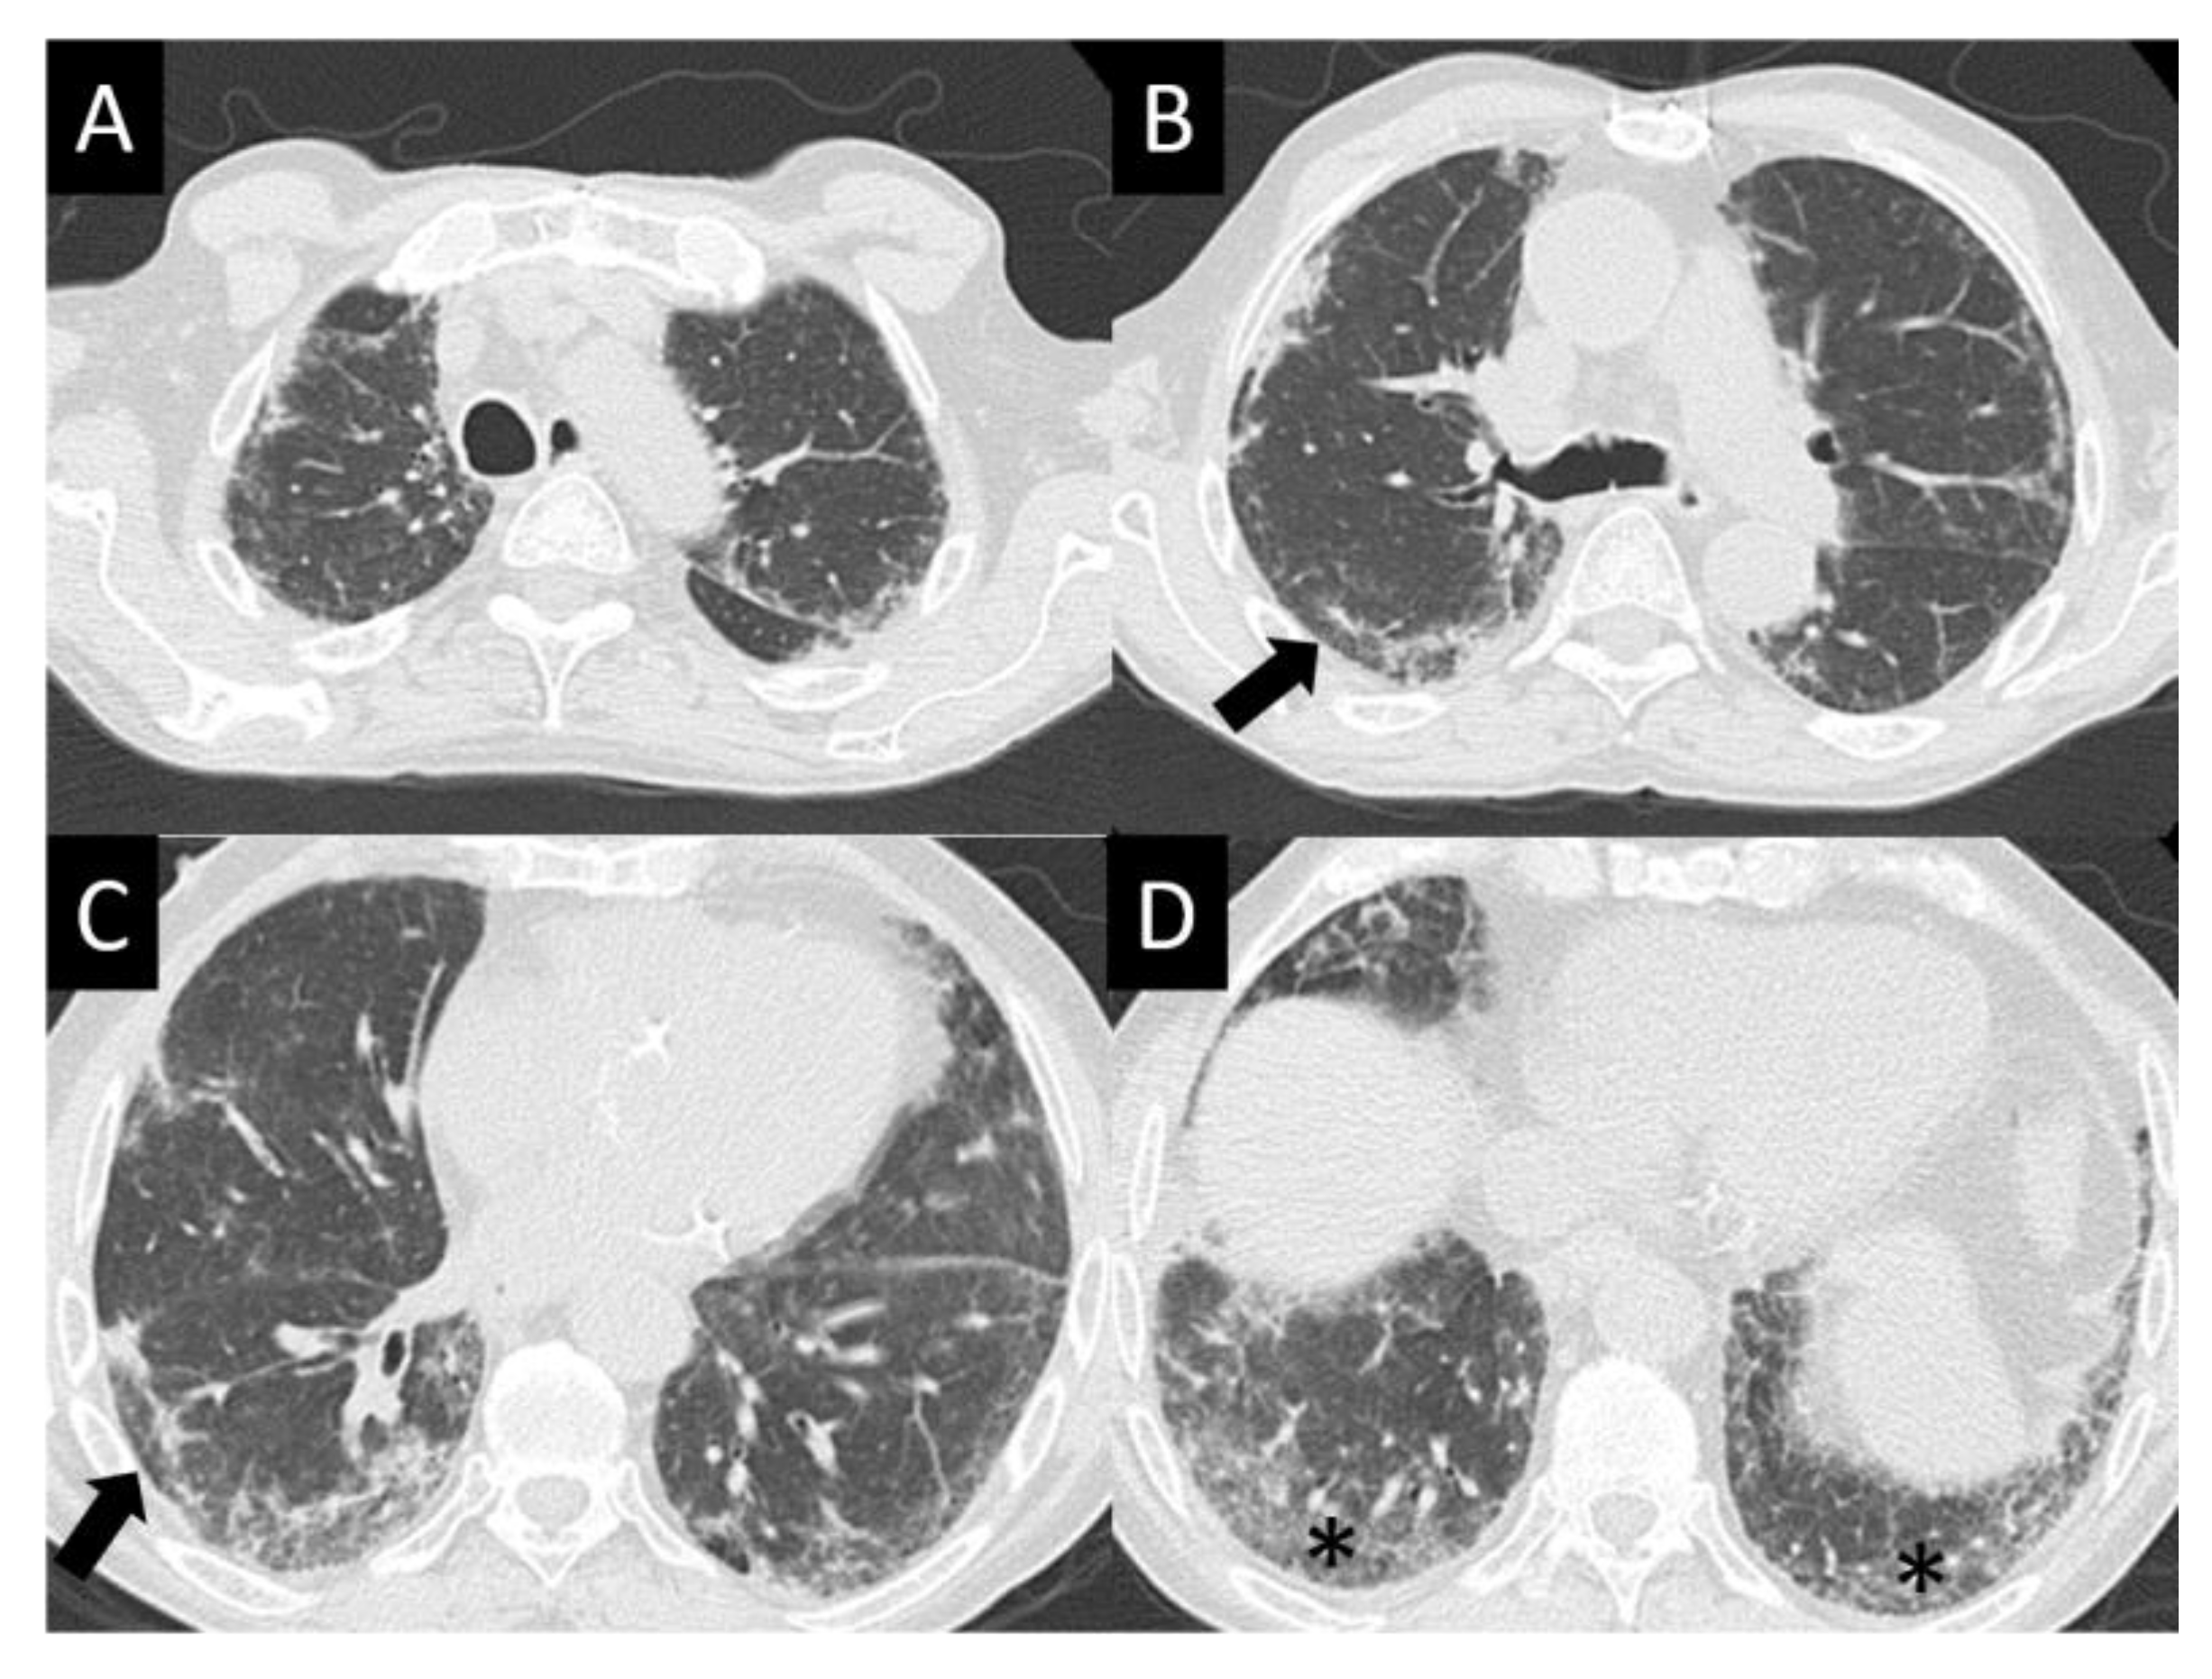

DAD is the most aggressive presentation and is usually present in grade 4 DI-ILD. Features of DAD on CT include ground glass opacities (GGOs) with associated areas of consolidative opacities (Figure 3). OP is characterized by multifocal areas of GGO and peripheral consolidation. Reversed halo/atoll signs may also be seen (Figure 4). NSIP is characterized by GGO, which tends to be basal with peripheral reticular opacities (Figure 5). Features of HP on CT include diffuse GGO, ill-defined centrilobular nodules, mosaic attenuation on inspiratory images, and air trapping on expiratory CT images (Figure 6).

Figure 5.

Nonspecific interstitial pneumonia (NISP). NSIP is characterized by ground glass opacity (GGO), which tends to be basal predominant with peripheral reticular opacities, seen in all images here (A–D) but best demonstrated in (D) (asterisk). Note sparing of the immediate subpleural lung in (B,C) (arrows), which is a hallmark of NSIP.